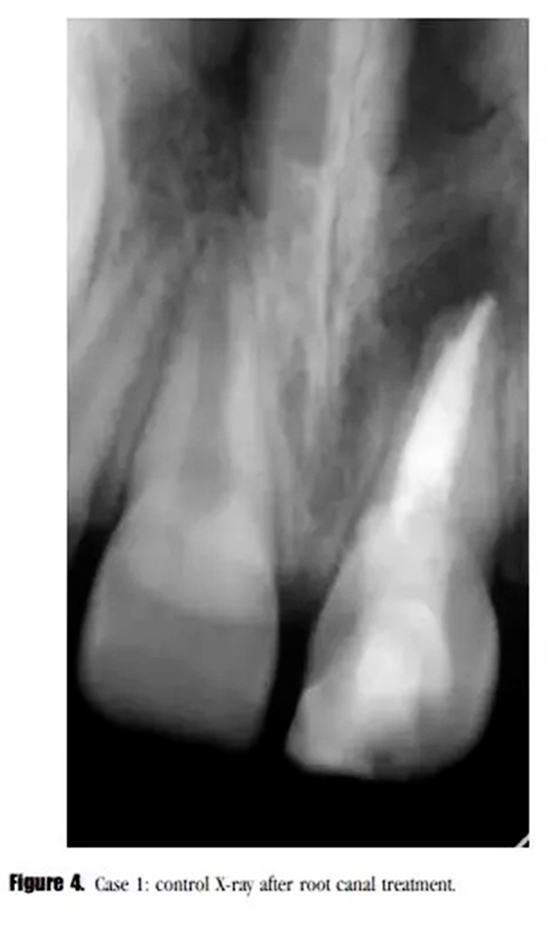

診斷為治療后的牙髓疾病復發(fā)。與患者家長商談,1個月后進行常規(guī)根管治療。根管內(nèi)使用 Total Fill RRM ( FKG Dentaire SA , La Chaux-de-Fonds , Switzeland )進行單尖充填(圖4)。

在3個月后的回訪中,患者癥狀消失,X線顯示根尖透射區(qū)域減小。(圖5)